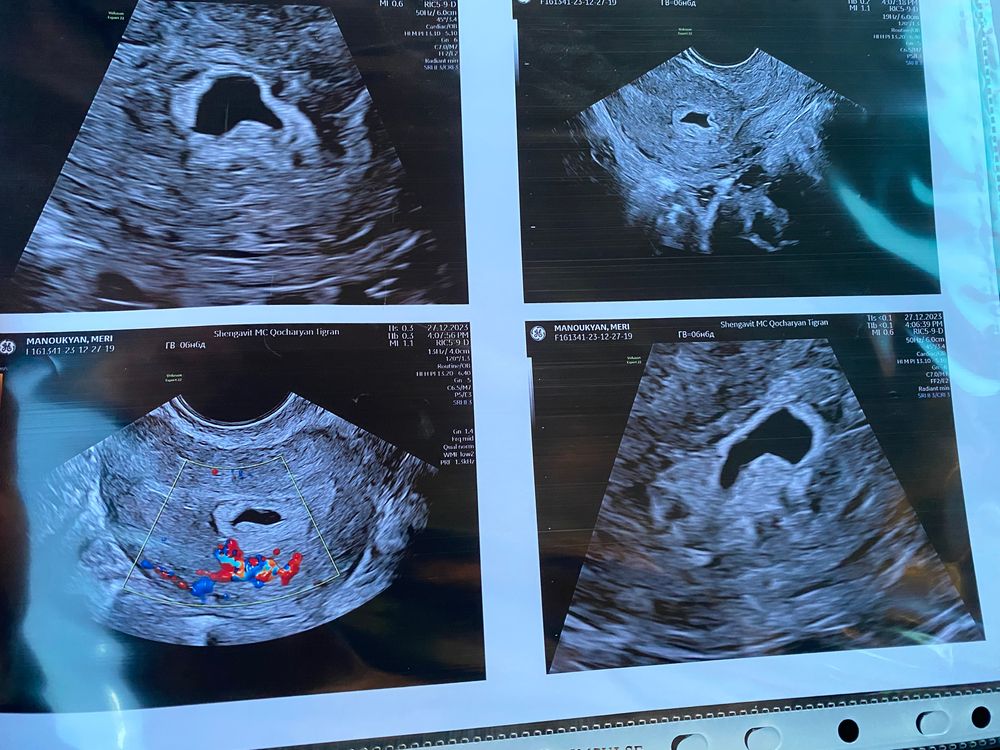

деформированный плодный мешок

А срок какой у вас? Оно какое-то пустое у вас и сверху 6,6 недель написано

Мэри Вит, так должен быть и желточный мешочек и эмбрион уже,а какой смысл пустое пя сохранять?Там нет никого и судя по тому что желточного мешочка нет и эмбрион не зародился,одно дело деформированное из-за тонуса,но при этом беременность нормальная,а другое потому что пустое пя деформируется, организм пытается избавиться от дефектной беременности

У меня было вытянутое по УЗИ, вот как на нижнем левом фото. Возможно, от тонуса. Но эмбрион был уже внутри, на сроке 6,5. Всё хорошо, родила.

Размеры ПЯ какие у Вас?